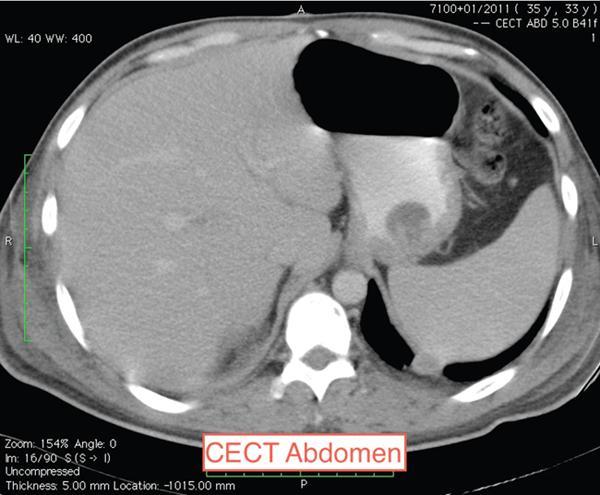

Midgut volvulus

Though it can occur at any age but it is most common in the neonate who has an associated GI malrotation.

In midgut volvulus, twisting of the intestine occurs. Apart from vomiting and abdominal distention, these patients may show evidence of hemodynamic collapse. If the volvulus has caused bowel ischaemia there can be presence of haematochezia as well.

Plain radiograph may show few air fluid levels or can be normal.

Barium study will show an abnormal location of the duodenojejunal junction to the right of the vertebral column at the level of the pylorus, indicating malrotation of the gut.

Abdominal Doppler can reveal the SMV lying in front of or to the left of the SMA indicating an inverse relationship of these vessels. CT abdomen can show clockwise twisting of the mesenteric vessels – the whirlpool sign.

Image

Fig. 7.4.1.5 CECT in a patient with midgut volvulus showing the whirlpool sign (clockwise twisting of the mesenteric vessels).